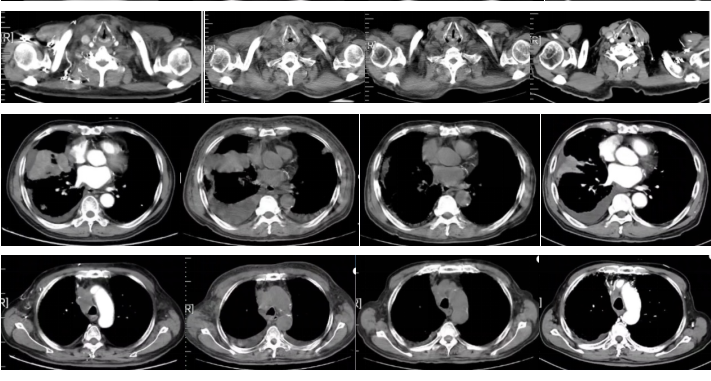

2周期斯鲁利单抗联合白蛋白紫杉醇治疗后,患者症状明显缓解。

图3

2022-09-17胸部平扫CT:恶性肿瘤维持性化学治疗后,较2022-7-20胸部CT旧片,右肺中叶占位(7.3×4.4cm)缩小;双肺部分结节增大;纵隔及右肺门淋巴结缩小;主动脉左侧旁(2-22)淋巴结稍增大:右侧胸腔积液增多;左侧新增胸腔积液;胸壁水肿增厚,双侧腋窝小淋巴结,请结合临床;余未见显著变化。附见,胰尾较前稍增粗:肝S4段新增低密度小结节,请结合腹部相关检查。

疗效评价:SD。

2022-11-16胸部平扫CT:恶性肿瘤维持性化学治疗后,较2022-9-16日胸部CT,右肺中叶占位(2.2×1.9cm)缩小;双肺大部分结节消失;右侧胸腔积液减少,左侧胸腔积液消失;纵膈及双侧腋窝淋巴结缩小;扫描层面内肝脏结节本次未见明确显示,胰腺结节缩小;余较前变化不大。

疗效评价:PR。